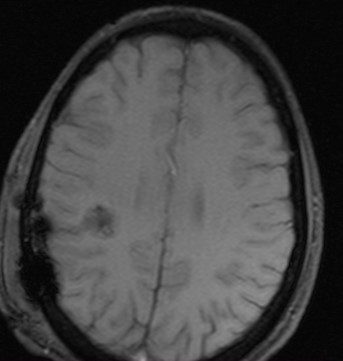

- Результат. В результате описанного метода было достигнуто радикальное и безопасное удаление каверномы, прилежащей к функционально значимой области головного мозга. В послеоперационном периоде отрицательной динамики в неврологическом статусе не отмечено. При контрольных КТ и МРТ головного мозга подтверждено радикальное удаление кавернозной мальформации. В удовлетворительном состоянии пациент выписан из стационара, вернулся к учебе в ВВУЗе.

Контрольные КТ и МРТ — состояние после удаления каверномы теменной доли без признаков осложнений.